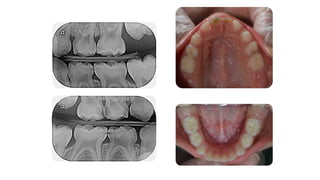

Manual Dexterity

• It is the ability to use your hands in a skillful, coordinated

way to grasp and manipulate objects and demonstrate small,

• A dentist must have superior manual dexterity skills.

and consider for a moment the size of the

average person's mouth.

• A dentist must be able to exercise very fine motor control